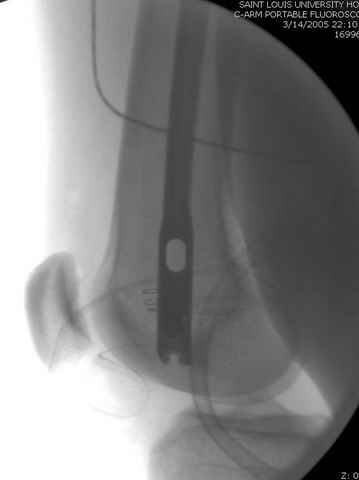

03.14.2005

больному 42, автоавария, политравма, открытая черепномозговая травма, безсознании, открытый перелом бедра, размозжение мягких тканей, дефект кожи на передней поверхности бедра около 13 см2 от ожога, компартмент синдром.

По поводу открытого перелома больной ургентно взят на ретроградное интрамедулярное штифтование, после рутинного дебрайдмента и фасциотомии на бедре и на голени.

перелом бедра

интраоперационные